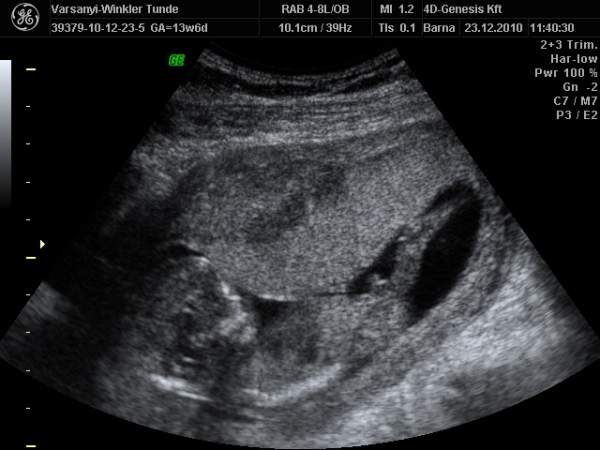

)2010.12.23 11:37